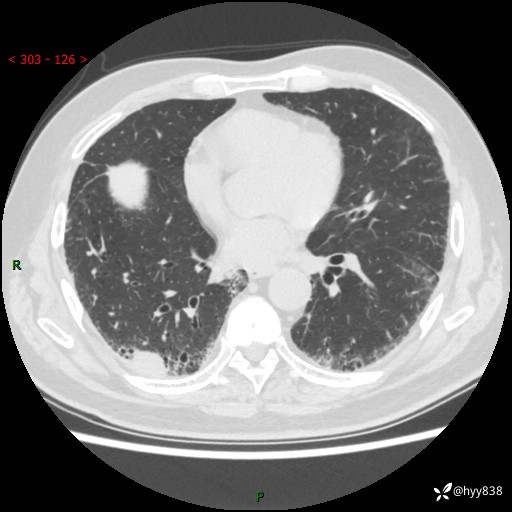

【现病史】:患者半月前无明显诱因出现咳嗽、咳痰,为白色粘痰,无明显加重与缓解因素,伴气促,无发热,无大量脓痰,无胸痛、咯血,无哮鸣音,到我院就诊,胸部CT示右肺结节增大,并口服药物治疗无明显好转,具体用药不详,为求进一步治疗随来我院,经门诊以“孤立性肺结节”收入我科。 病程中患者精神、饮食可,睡眠不佳,大小便正常,体力下降,体重未见明显下降。

【检查】:胸部CT平扫+增强